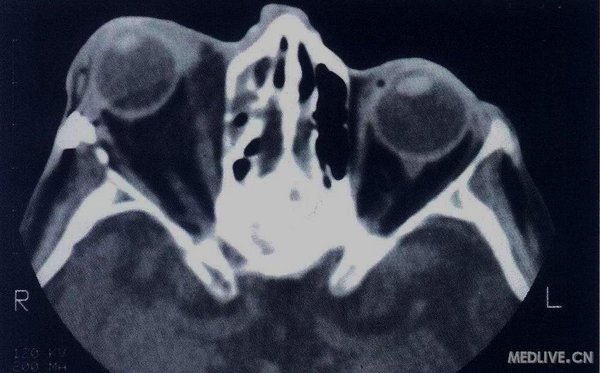

眶蜂窝织炎CT

显示右眼眼球突出和副鼻窦炎,符合眼眶蜂窝织炎的诊断